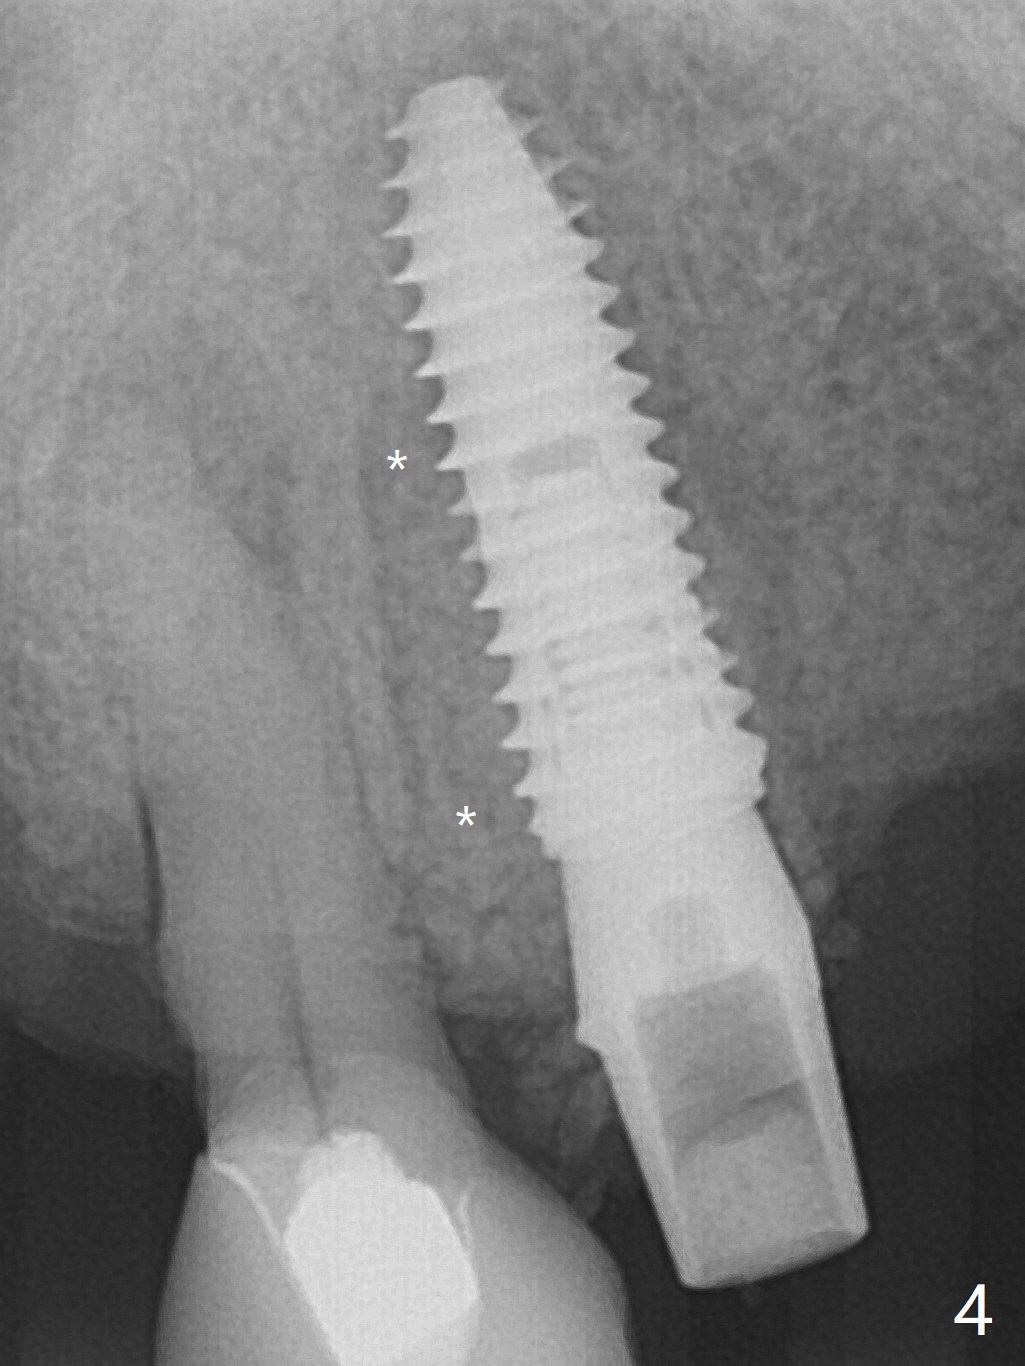

部分断裂的5号牙颊侧根尖有3个瘘道(图一),五类(颈部)缺损,严重牙龈退缩。牙齿拔除过程中断裂,需要手机切断拔除,颊侧骨板缺失,钻洞起源于牙槽窝腭侧(融合根,图二,五),植入4x13毫米长植体,根尖骨大约4毫米,植体也卡入近中,远中骨壁,扭力大于35Ncm,即刻放置基台,颊侧间隙(图三至五:*)放入粘性骨粉,牙槽窝口用PRF穿过基台关闭(图五),接着制作临时牙冠(图六:T),多次衬里严密关闭牙槽窝,而咬合面低,最后插入活动托牙(图七:RPD,左侧有两个基牙)。Return to Protect Graft Torque Xin Wei, DDS, PhD, MS 1st edition 05/18/2021, last revision 05/18/2021